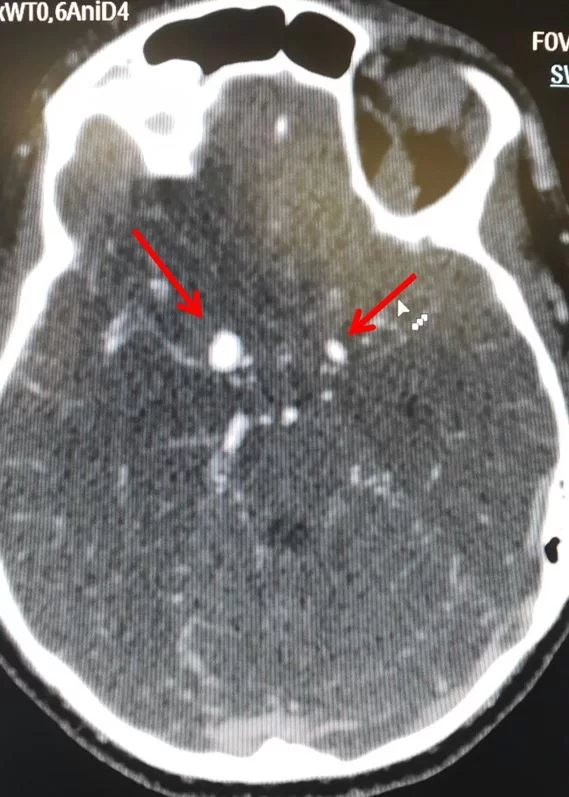

Η διάγνωση συνήθως ξεκινά με τον απεικονιστικό έλεγχο, δηλαδή με αξονική ή/και μαγνητική τομογραφία. Συνήθως χρησιμοποιούνται και ειδικές ακολουθίες δηλαδή ειδικές απεικονίσεις οι οποίες δείχνουν καλά τα αγγεία του εγκεφάλου (Εικόνα 2). Στις περιπτώσεις όπου υπάρχει έντονη η υποψία ανευρύσματος, αλλά οι απεικονιστικές εξετάσεις είναι αρνητικές, ίσως χρειαστεί να γίνει οσφυονωτιαία παρακέντηση. Κατά την οσφυονωτιαία παρακέντηση λαμβάνεται εγκεφαλονωτιαίο υγρό από το σπονδυλικό κανάλι με τη βοήθεια μιας βελόνης, και το υγρό εξετάζεται για ερυθρά αιμοσφαίρια.

Πολύ συχνά –και ειδικά στην περίπτωση που η αξονική ή η μαγνητική δείξουν κάποιο πιθανό ανεύρυσμα– πρέπει να γίνει και αγγειογραφία εγκεφάλου. Με αυτή την εξέταση απεικονίζονται όλα τα αγγεία του εγκεφάλου με μεγάλη ακρίβεια. Η αγγειογραφία δείχνει πολύ καλά το μέγεθος και το σχήμα του ανευρύσματος και βοηθά στον σχεδιασμό των περαιτέρω θεραπευτικών χειρισμών.